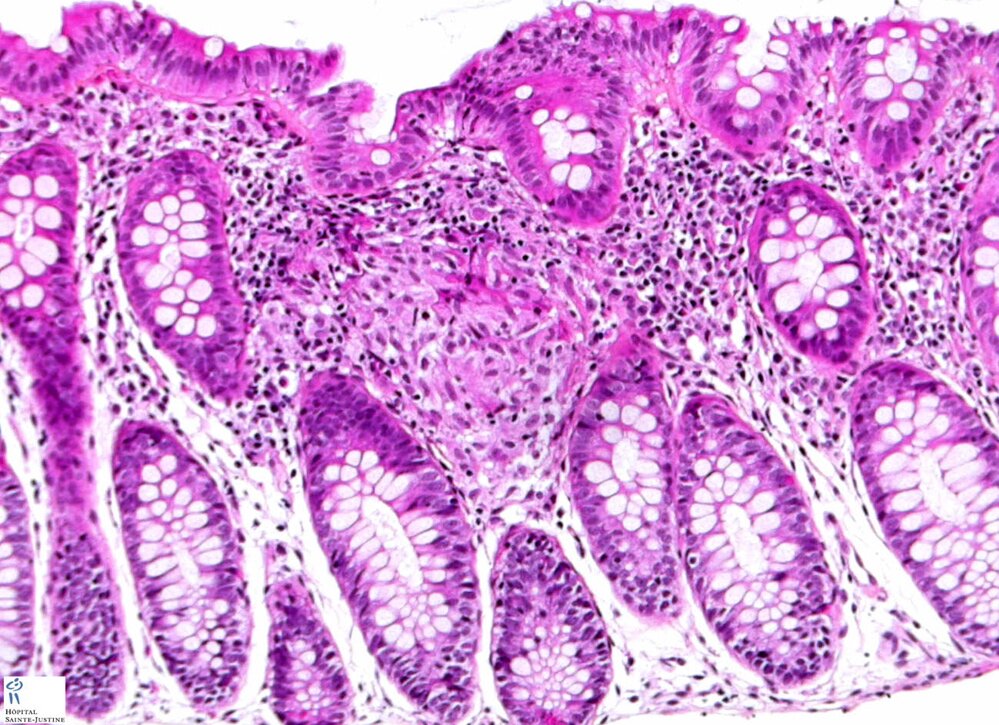

colonic Crohn disease

tuberculous colitis

colonic sarcoidosis